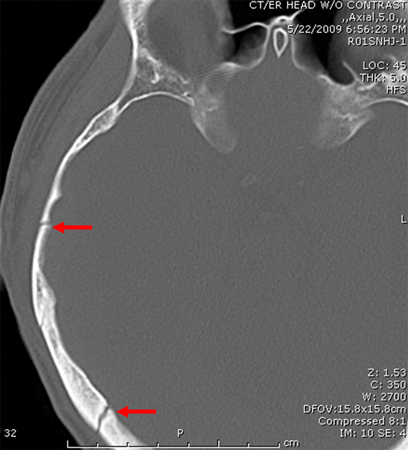

[Figure caption and citation for the preceding image starts]: Axial CT scan demonstrating open elevated linear skull fracture (large arrow). Note the air in the soft tissues (small arrow), the small amount of pneumocephalus associated with the fracture (circle), and that the level of elevation of the bone fragment is significantly more than the thickness of the bony tableFrom the teaching collection of Demetrios Demetriades; used with permission [Citation ends].